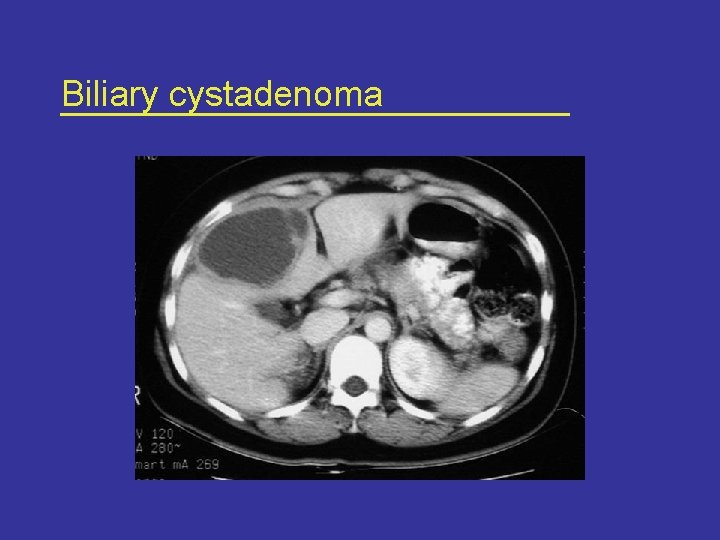

Radiological features • USG and CT are complementary* – – – Internal septations Thickened and irregular wall Mural nodules and papillary projections Calcifications Wall enhancement * Korobkin et al AJR Am J Roentgenol Sept; 153(3): 507 -11, 1989

Radiological features Ultrasonography CT scan

Biliary cystadenoma